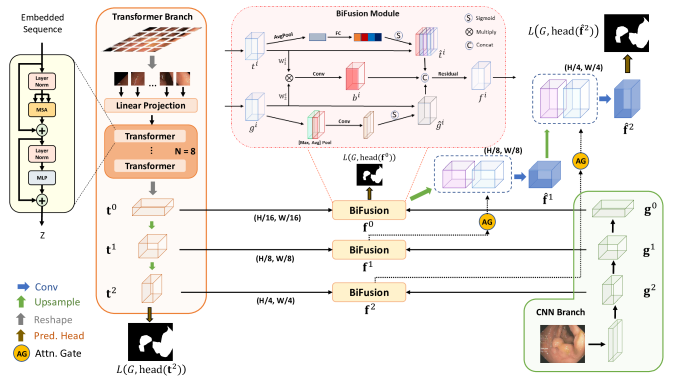

FAT-Net 属于最早期应用 Transformer 架构的经典医学图像图像分割网络,致力于解决皮肤病变分割任务。整个网络基于编解码架构,编码器部分采用 Transformer + CNN 的并行双分支架构进行主要的特征提取,以有效地捕获远程依赖关系和全局上下文信息。随后,基于特征重标定的策略对来自不同架构所提取到的的特征图进行更深层次的融合,通过学习的方式来自动获取到每个特征通道的重要程度,最后再筛选出更加有用的特征图。最后,通过在跳跃连接部分集成了特征自适应模块(FAM)来激活有效通道和抑制不相关的背景噪声,从而增强相邻层特征之间的特征融合。